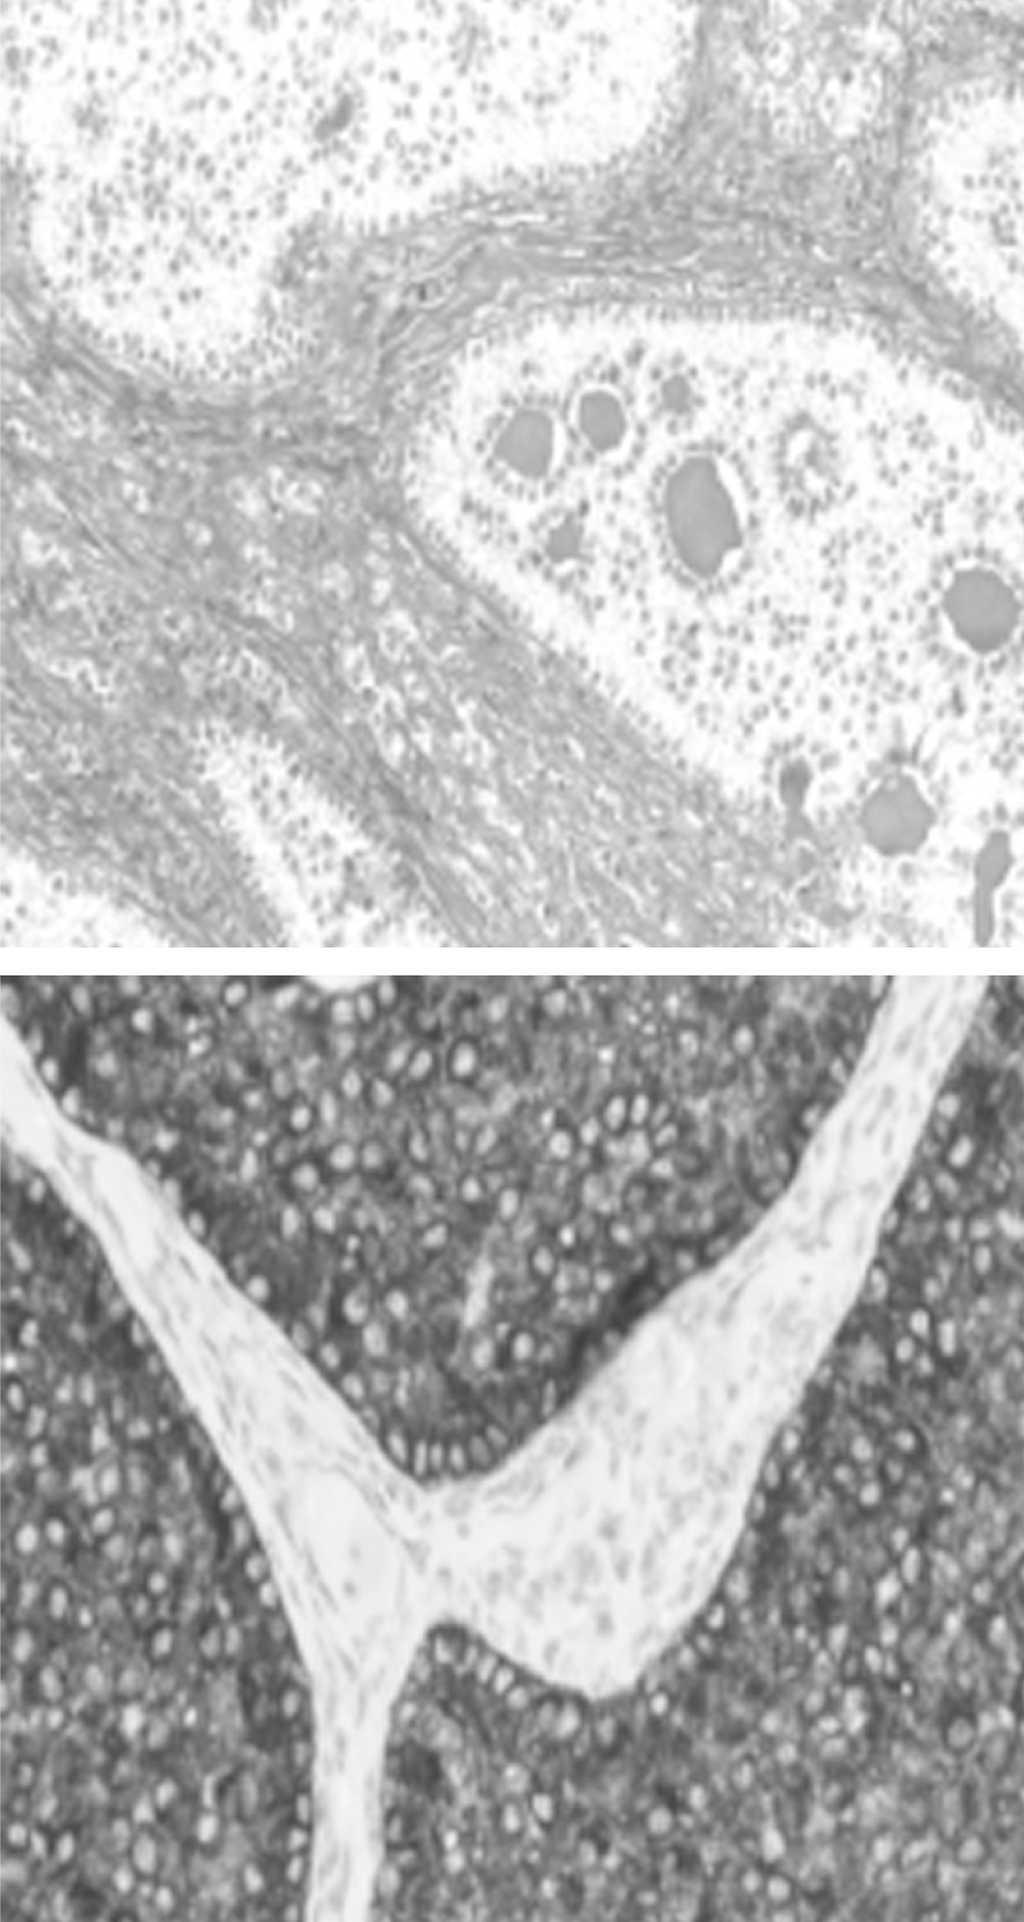

El informe anatomopatológico definitivo informaba de un ovario de 88 g, blanquecino, brillante y de superficie lisa. Al corte se describía como una masa sólida, constituida por tejido pastoso amarillento con áreas de hemorragia, cubierta por una cápsula de 1-2 mm de grosor. El tumor estaba constituido por una proliferación de células de distinto tamaño y citoplasma claro, organizadas en racimos. Dentro de la células se podían ver estructuras anulares con material eosinófilo parecidas a la membrana basal. Estas estructuras a su vez estaban rodeadas de células cilíndricas con núcleo pálido. Los nidos neoplásicos celulares estaban claramente diferenciados del estroma ovárico. Sin embargo, pudimos observar células en cadena dentro del mismo estroma. El tumor estaba bien encapsulado dentro de una cápsula fibrótica, en algunas áreas claramente preservado del parénquima ovárico. No se evidenció invasión capsular. Los análisis inmunohistoquímicos revelaron intensa positividad para la α-inhibina (fig. 1), positividad moderada para la vimentina y negativa para la queratina S-2.

Figura 1.A: tumor con hematoxilina-eosina. B: tumor con inhibina.

En uno de los ganglios paraaórticos se observó una micrometástasis subcapsular menor de 2 mm de células de los cordones sexuales con diferenciación anular (fig. 2). Los lavados y el epiplón fueron ambos negativos.

Figura 2. Metástasis subcapsular de ganglio paraaórtico.